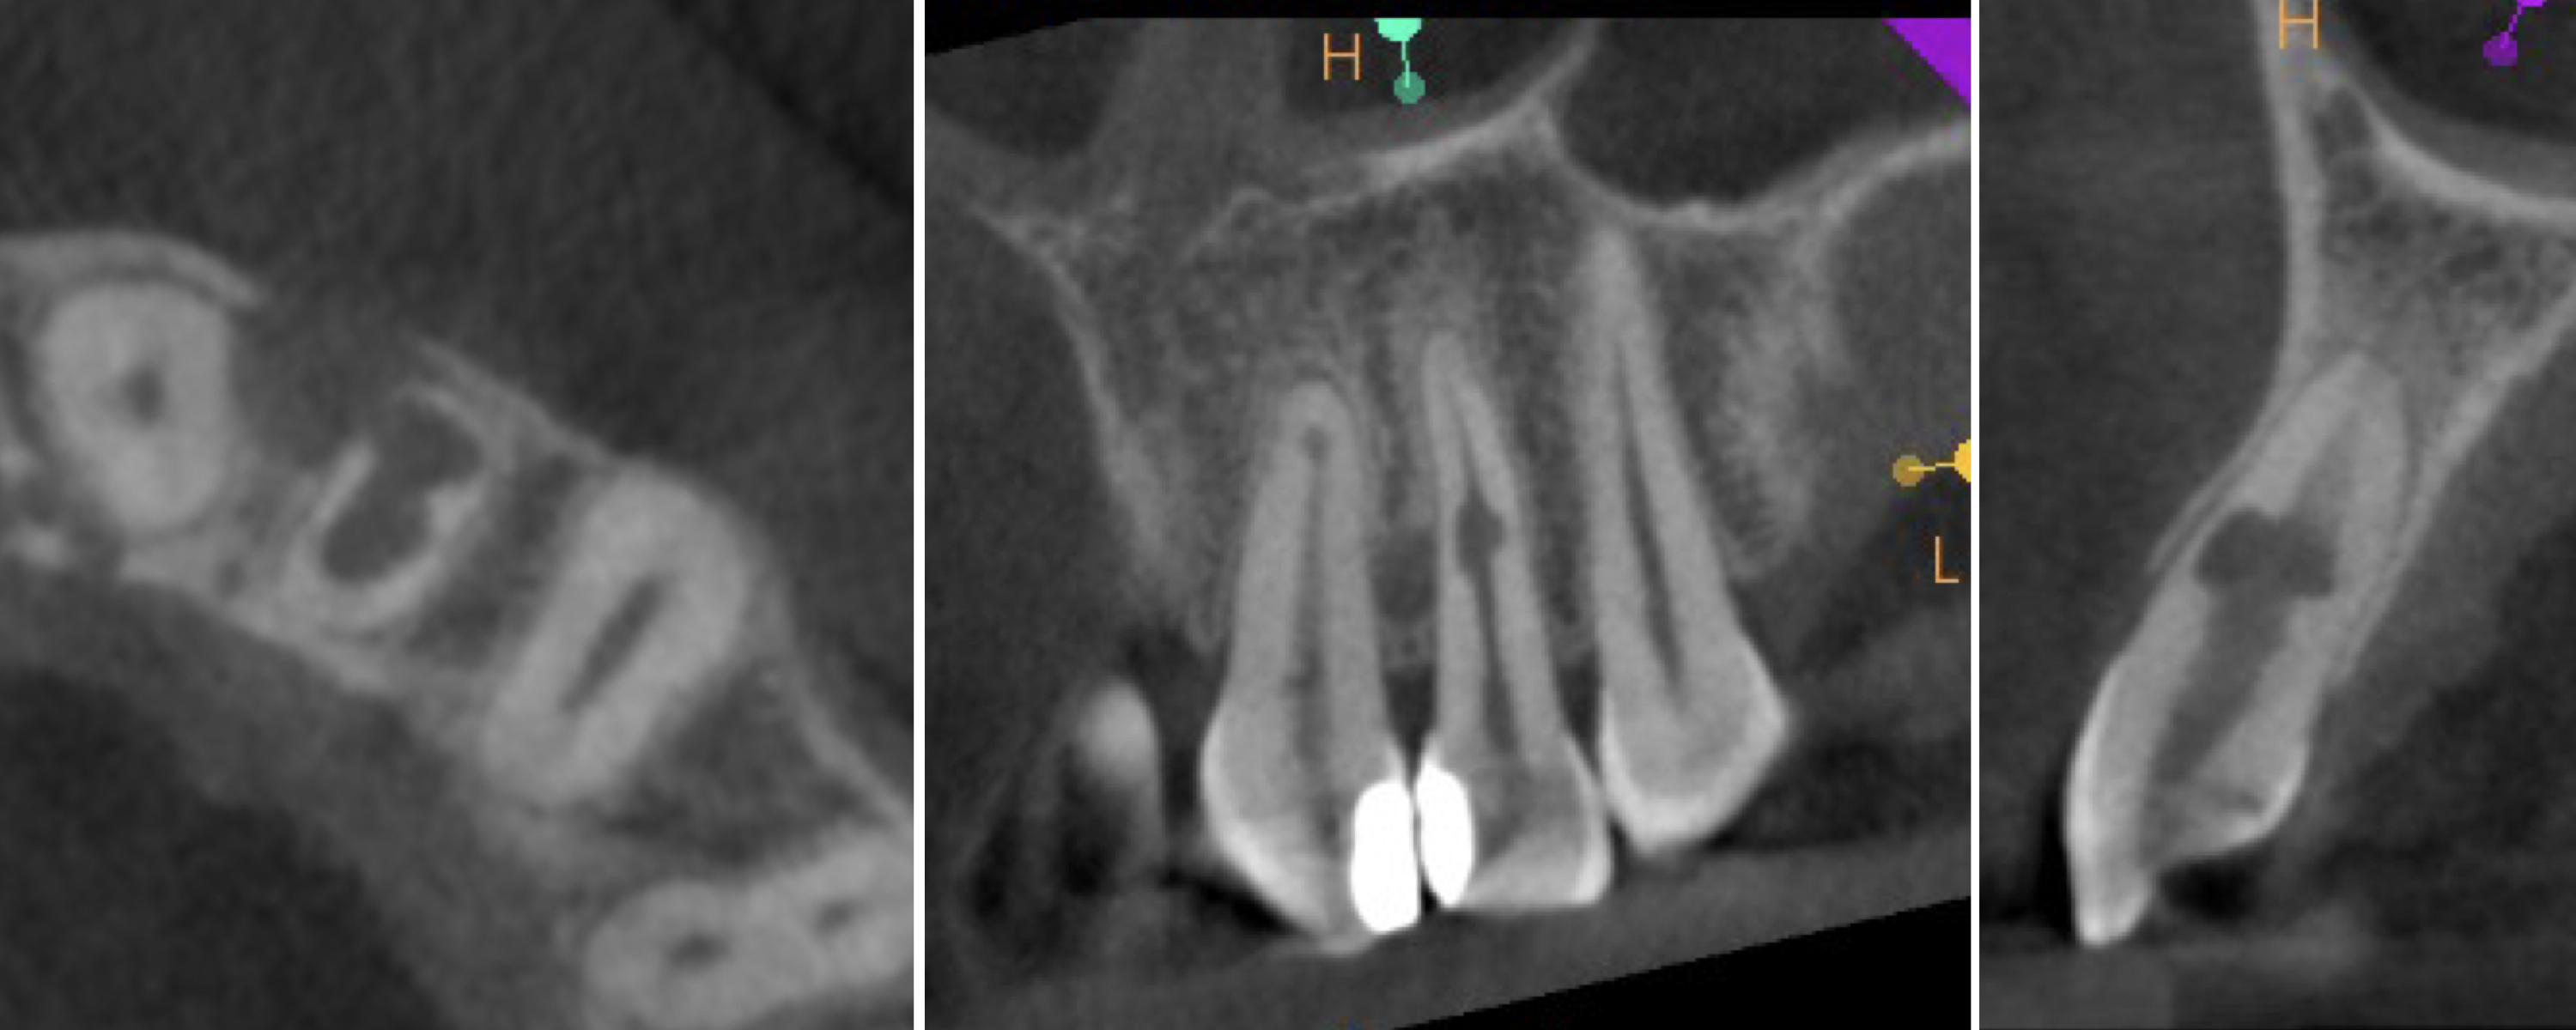

Recall appointments was performed after two (Figs. 16a & b) and four years (Figs. 17a & b). The radiographic examination showed the presence of bundle bone. The periodontal status was stable, and the tooth remained asymptomatic.

Figs. 17a & b: CBCT scan taken four years after the treatment.